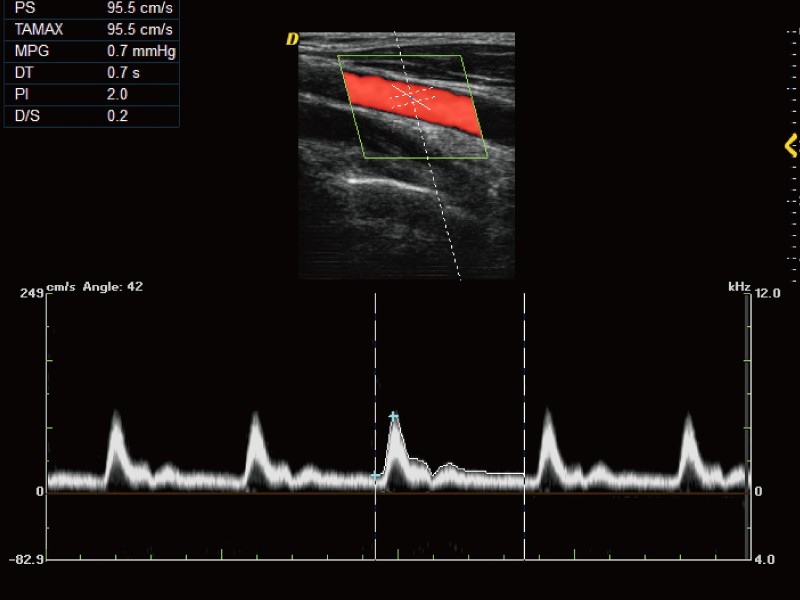

パルス波(PW)

オートトレース